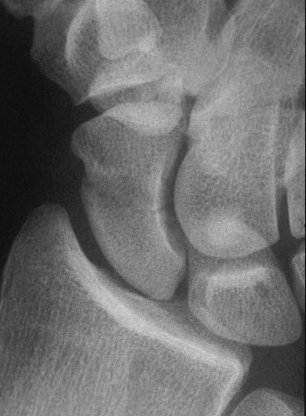

Late, with asymptomatic partial union or nonunion, but no haloing.

Click for larger image